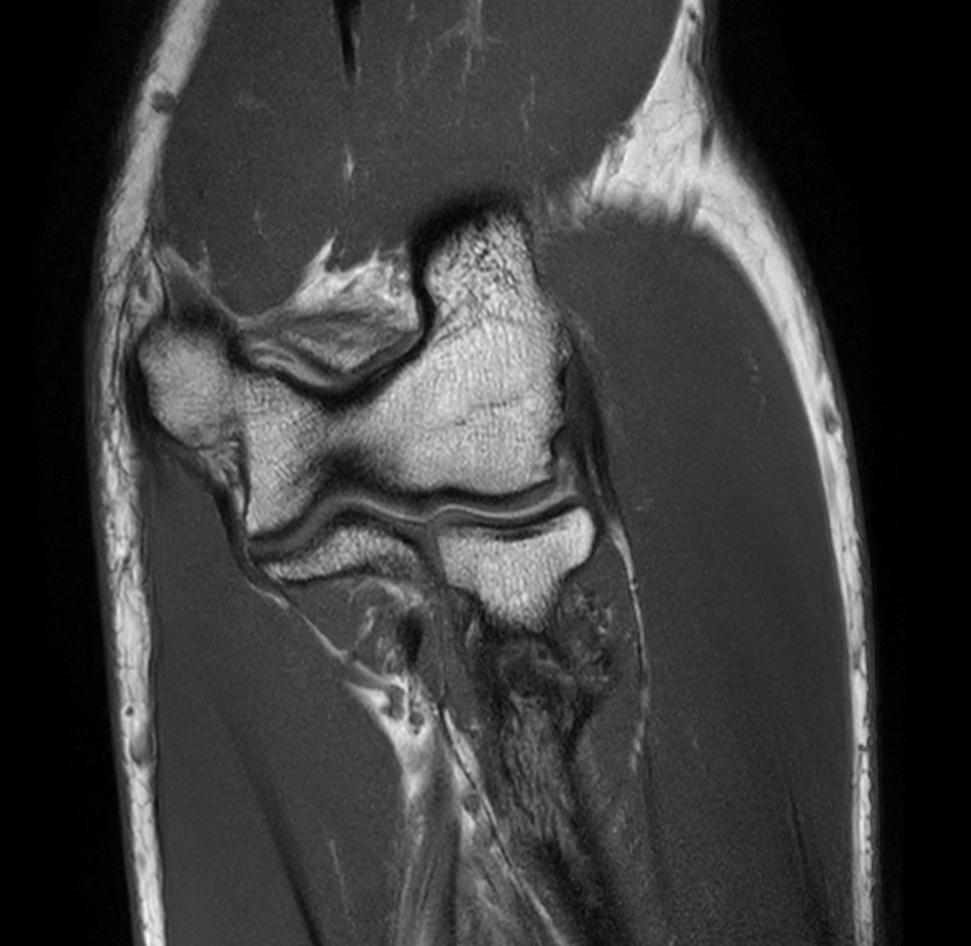

Sagittal PDw SPAIR